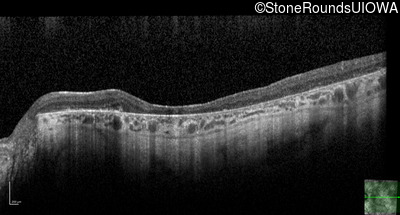

Age at visit: 38 years

This 38 year old woman had normal vision until age 22 when she noticed poor night vision when working as a camp counselor after college. Her hearing loss was first noticed at age 3 and was correctable with hearing aids.

Age at visit: 38 years (Visit 2)